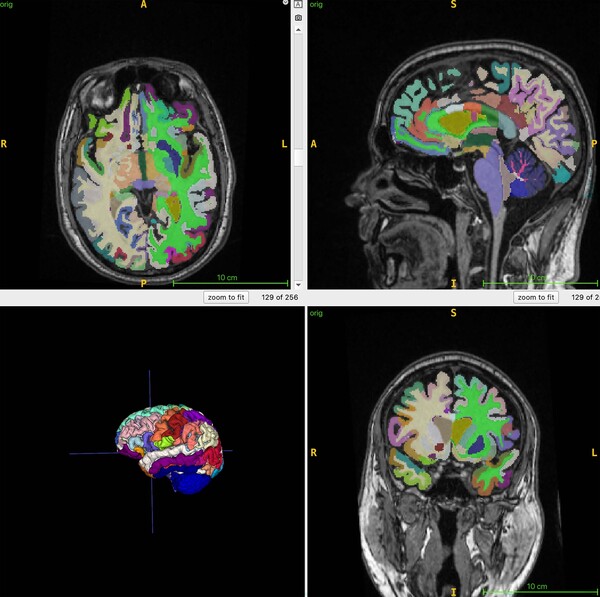

연구팀은 이 연구에서 뇌의 구조적 MRI 영상의 부위별 부피를 기반으로 추정한 뇌 나이와 전신 MRI로 측정한 총근육량과 내장지방, 피하지방 사이의 연관성을 인공지능 알고리즘으로 분석했다.

이들은 4개 지역 거주자 1,164명(평균 나이 55.17세)을 대상으로 전신 MRI를 촬영하고 이를 지방과 체액, 근육 등이 다른 색으로 보이게 하는 기법과 결합해 총근육량과 내장지방 피하지방, 뇌 나이를 정량화했다.